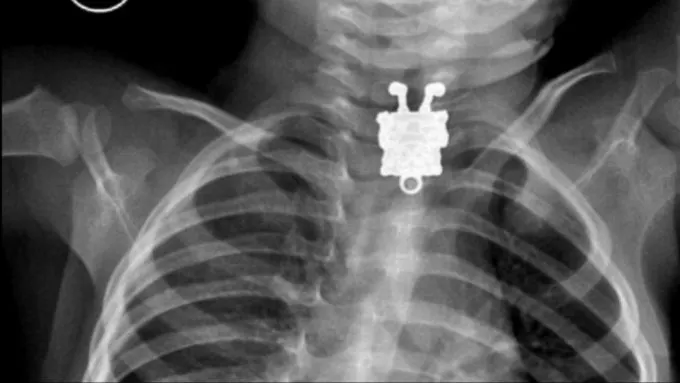

Оказывается, в LEGO специально добавляют сульфат бария, благодаря чему мелкая деталь, хоть и изготовленная из пластмассы, просвечивается на рентгене. Гениально!

Так вот — всё просто, при производстве оригинального конструктора Lego в пластик добавляют сульфат бария, благодаря которому детали видны на рентген-снимках.